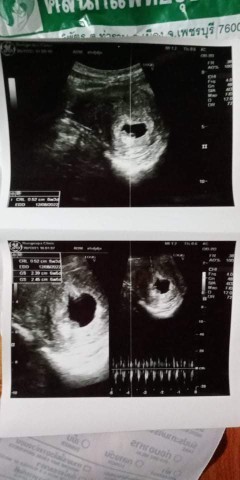

กี่ weeks ถึงจะตรวจเจอการเต้นของหัวใจลูกน้อยคะ

ตอนนี้น้อง 6 weeks 2 days